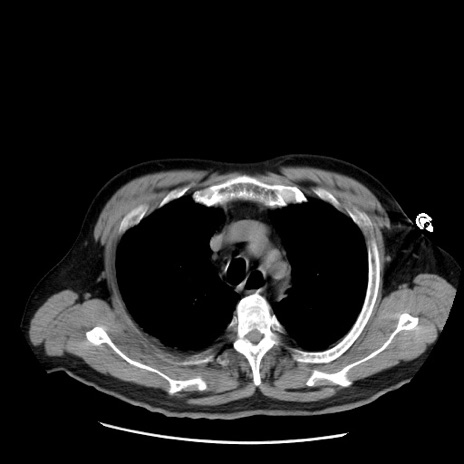

症例20(横断像)

【症例】 60歳代男性

【主訴】 腹部膨満、嘔吐

【現病歴】5日前頃より倦怠感を認め食事量減少し4日前の朝嘔吐、食事摂取困難となった。 3日前近医受診し点滴施行され整腸剤などを処方された。 当日他院を受診し、腹部膨満著明、炎症反応の上昇(CRP10.8、WBC11200)あり、紹介受診となる。

【身体所見】 意識JCS1 受け答えがはっきりしないBP 111/57mHg、 P 67bpm、、BT35.2°C、SpO2 97%(RA)、 腹部:膨隆、打診で鼓音あり、全体的に圧痛有り、腸蠕動音(-)、反跳痛ははっきりせず。

【データ】WBC 11400、CRP 14.20